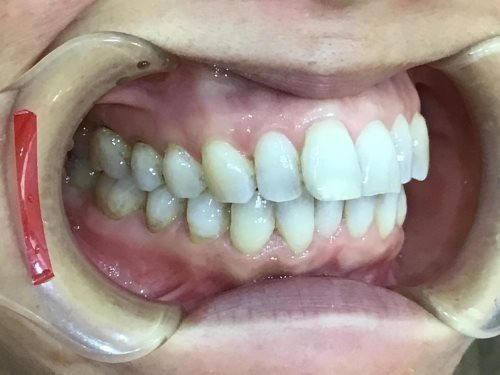

右横